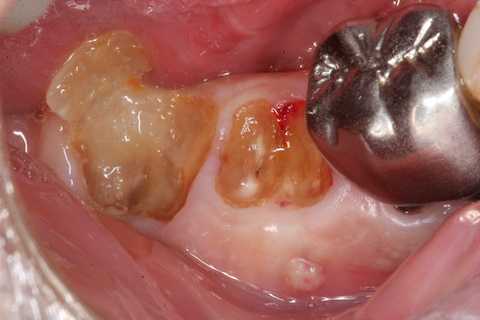

今日も野戦病院シリーズ26(CK破折) 2025.10.25